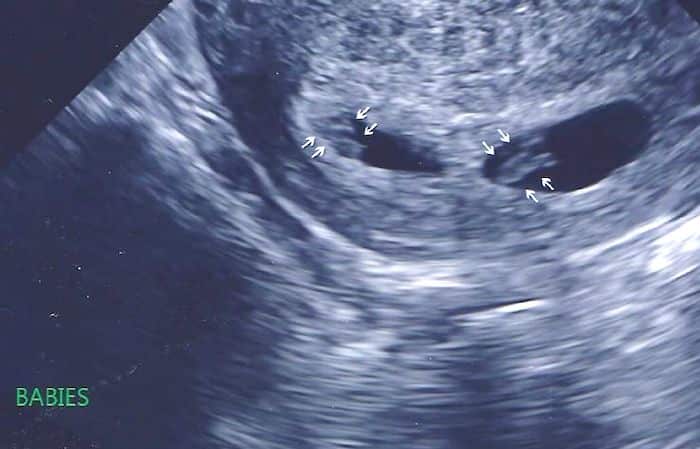

Early Twin Ultrasound at 7 Weeks

The earliest your doctor would likely order an ultrasound confirming twins would be 4 weeks pregnant. But unless you are going through fertility treatments, doing an ultrasound before 6 weeks isn’t very common, with the exception of complications. Women who are going through fertility treatments or have early complications may be able to have an early twin ultrasound at 4 or 5 weeks pregnant and find out they are pregnant with twins.

At four to five weeks after a pregnant woman’s last period the ultrasound commonly shows a small collection of fluid within the lining of the uterus that represents the early development of the gestational sac. At about five and a half weeks after a pregnant woman’s last period the ultrasound typically shows a gestational sac and within it we can see a 3-5 mm bubble-like structure, which is the yolk sac. At approximately six weeks after a pregnant woman’s last period, we can see a small fetal pole, one of the first stages of growth for an embryo, which develops alongside the yolk sac.

Can You Tell at 7 Weeks if Its Twins?

Yes! You’d need to have an ultrasound at 7 weeks to confirm a twin pregnancy. Your twin belly at 7 weeks may not look like much of a belly at all, so getting in to your doctor for an ultrasound is key to find out if you’re really having twins.